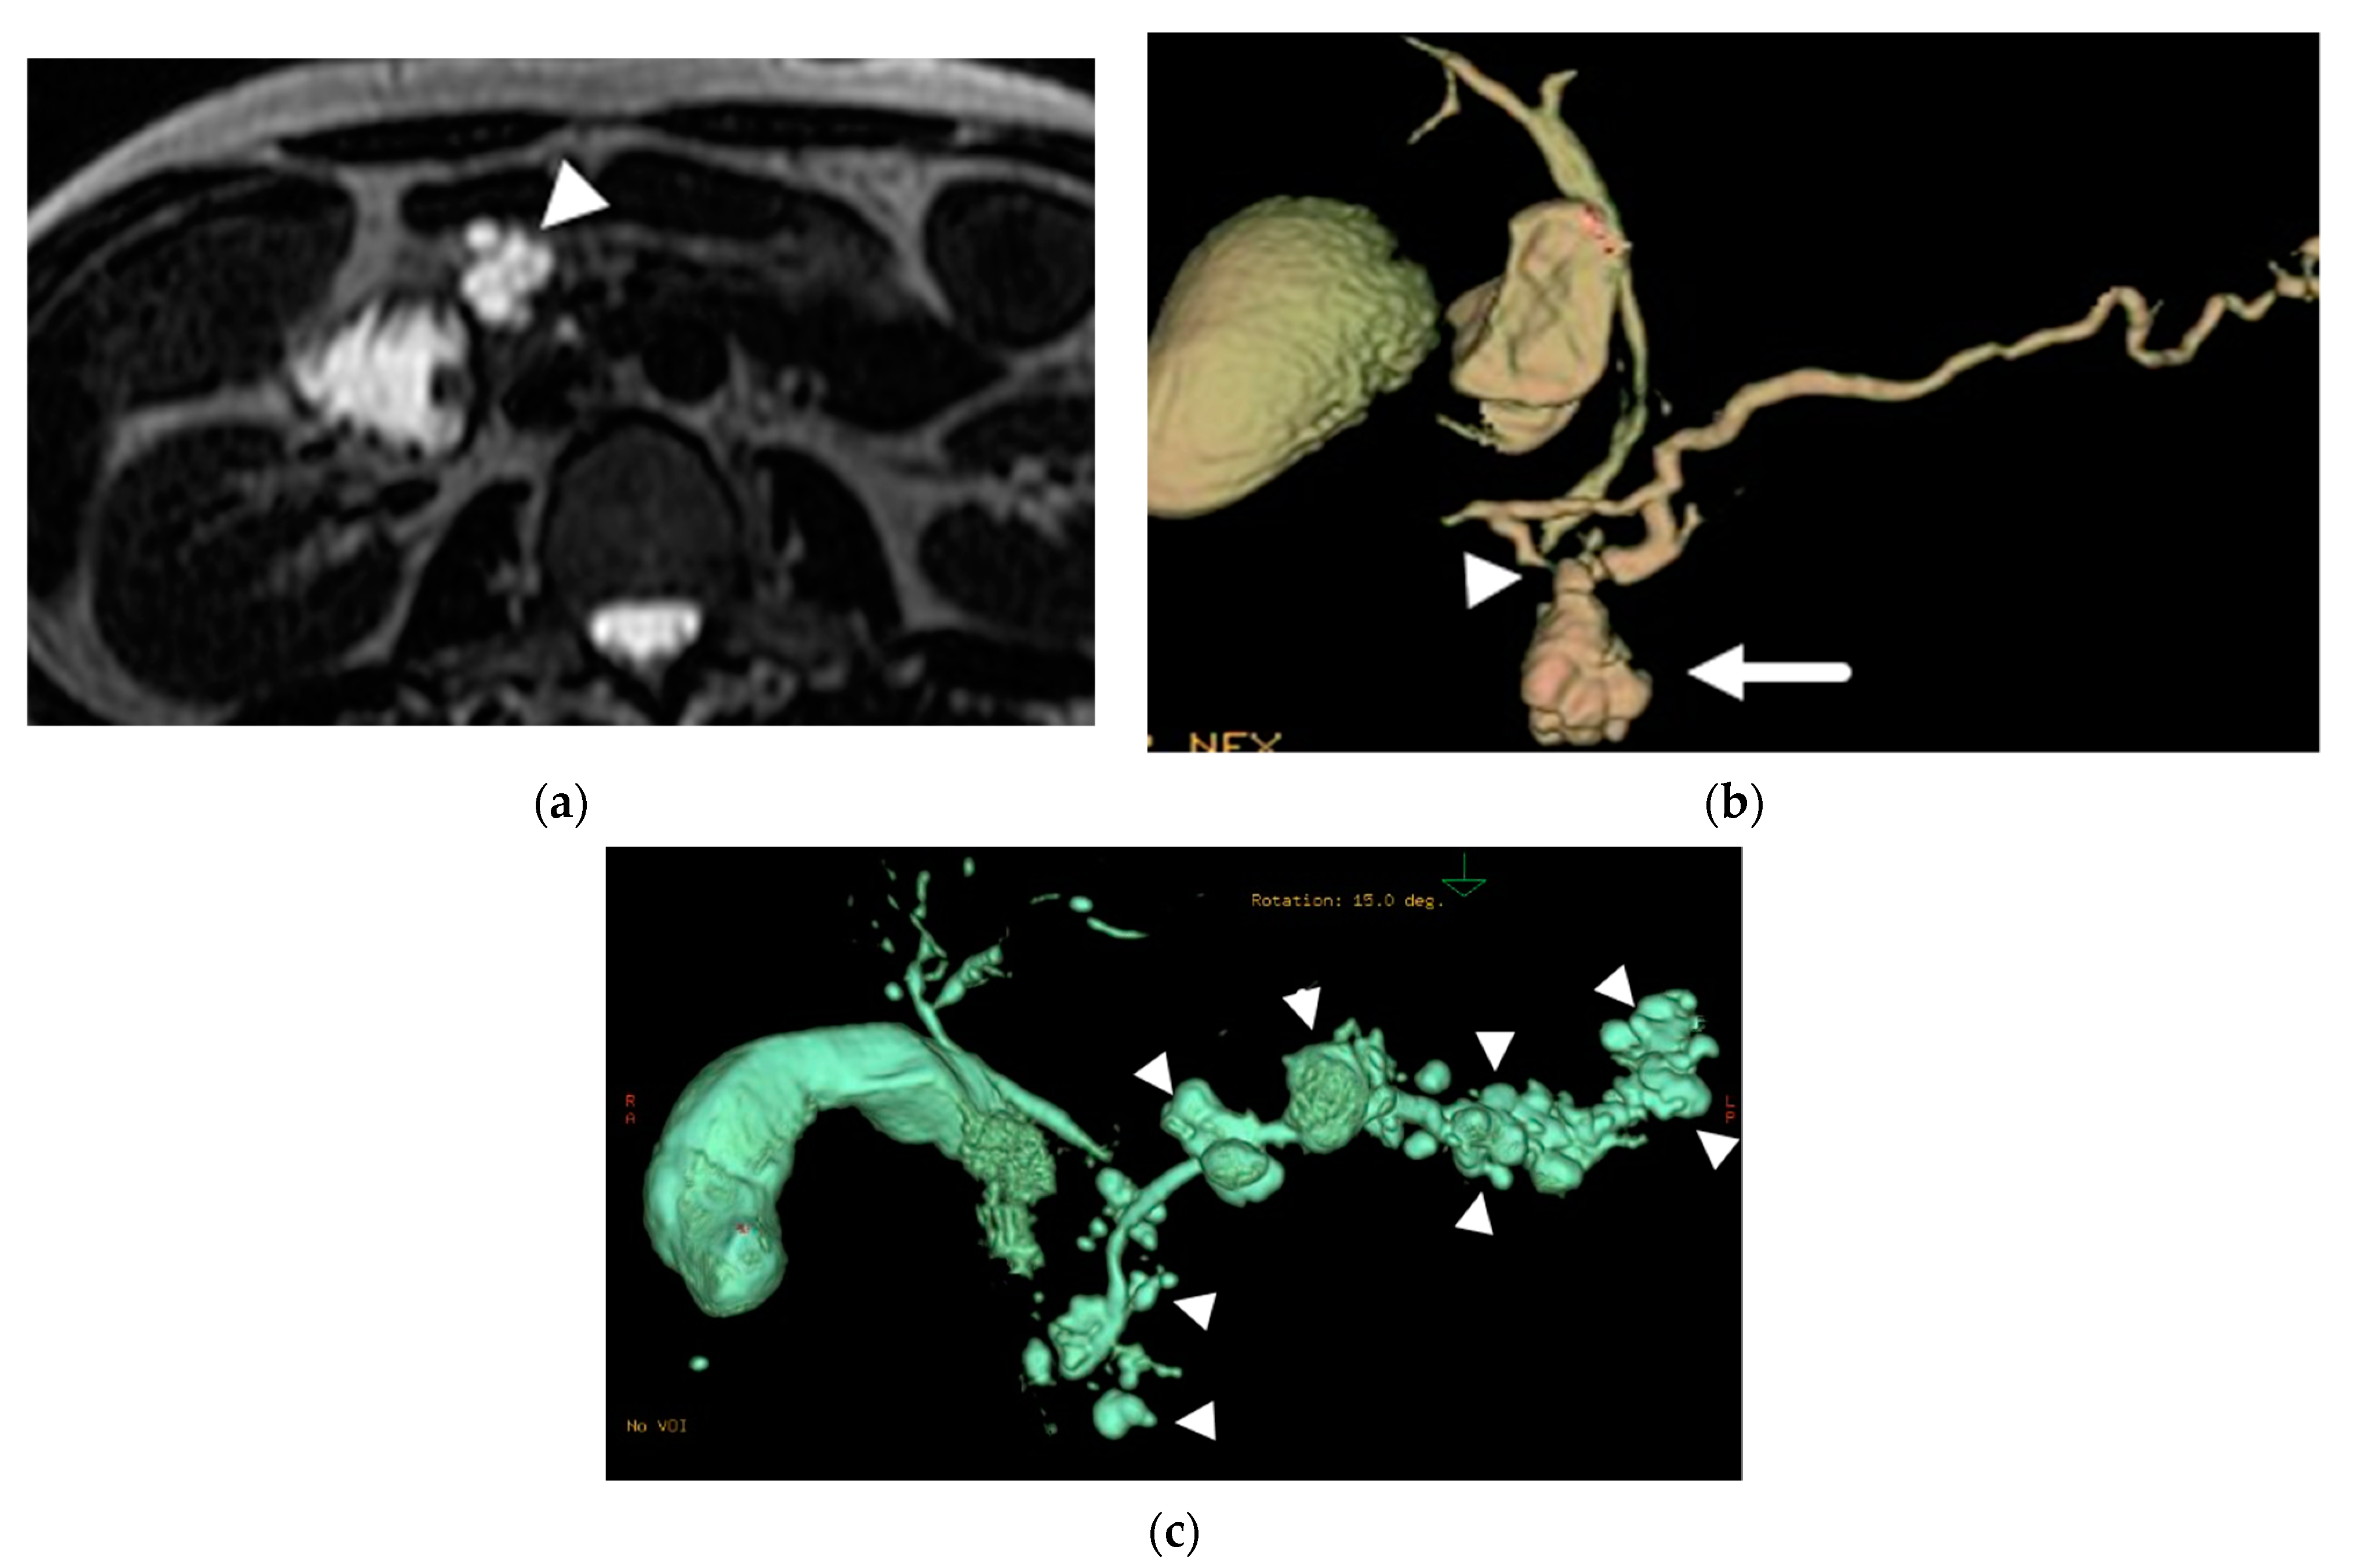

- Mamone, G.; Barresi, L.; Tropea, A.; Di Piazza, A.; Miraglia, R. MRI of mucinous pancreatic cystic lesions: A new updated morphological approach for the differential diagnosis. Updates Surg. 2020, 72, 617–637. [Google Scholar] [CrossRef] [PubMed]

- Cantisani, V.; Mortele, K.J.; Levy, A.; Glickman, J.N.; Ricci, P.; Passariello, R.; Ros, P.R.; Silverman, S.G. MR imaging features of solid pseudopapillary tumor of the pancreas in adult and pediatric patients. AJR Am. J. Roentgenol. 2003, 181, 395–401. [Google Scholar] [CrossRef]

- Yu, M.H.; Lee, J.Y.; Kim, M.A.; Kim, S.H.; Lee, J.M.; Han, J.K.; Choi, B.I. MR imaging features of small solid pseudopapillary tumors: Retrospective differentiation from other small solid pancreatic tumors. AJR Am. J. Roentgenol. 2010, 195, 1324–1332. [Google Scholar] [CrossRef]